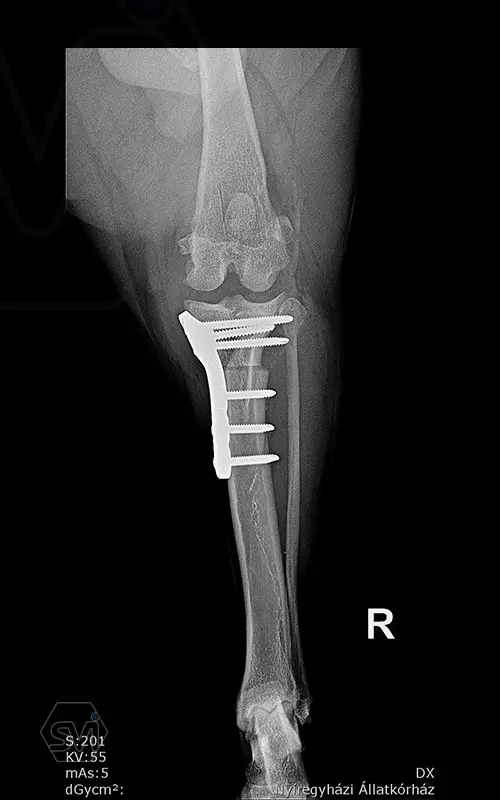

1,5 year old 13 kg mix dog underwent surgery today due to cranial cruciate ligament rupture and concomitant grade 3/4 medial patella luxation. During surgery, lateral tightening and medial loosening of the joint capsule (without opening the capsule) was performed. In the first phase of surgery, the 26-degree TPA was corrected simultaneously with the medial transposition of the proximal fragment. An R18 TPLO blade was used and the step and the rotation was fixed with a 2.7 precontured TPLO plate. The big curvature of the precontured plate provided an opportunity for placement without further conuring of the plate. The plate was temporarily fixed to the bone surface with two 1.2 K-nails using holes for temporary fixation. The distal piece was first stabilized with two locking screws. An AO 2,7mm srew was placed in the cranial hole of the proximal piece, which was able to create a significant tuberositas tibiae shift by tightening and simultaneously removing the temporaly, rotation stabilizing K-wire. Polyaxial locking screws are inserted into the remaining holes.

Thus, during surgery, we successfully applied a member of the precontured plate family designed for 2.7 mm screws for TPLO-M surgery.